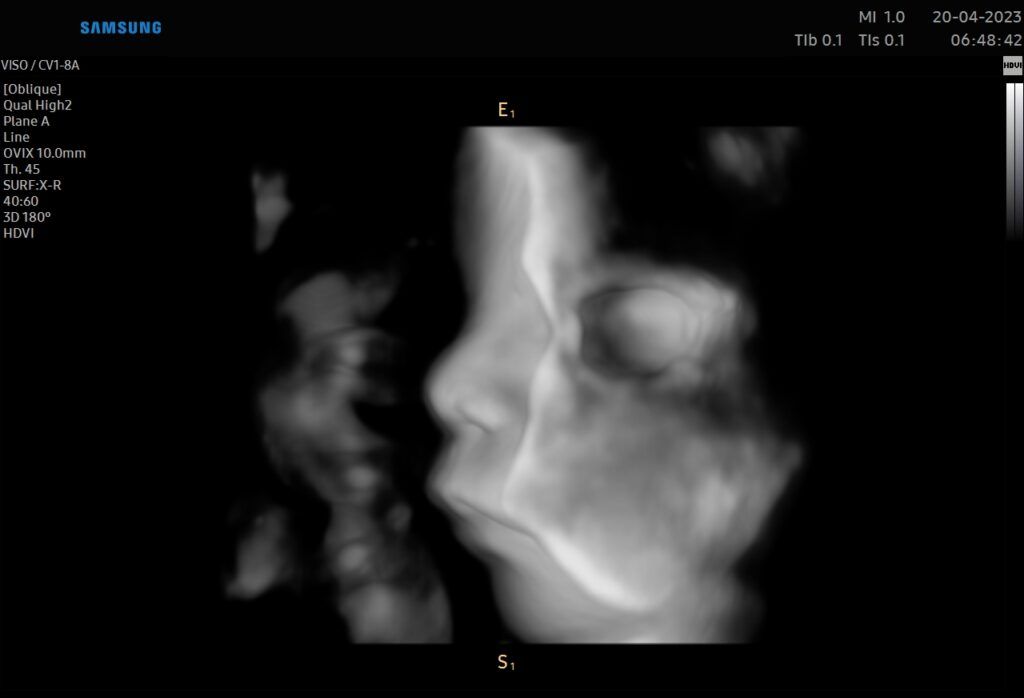

• Ecografia tridimensionale, Ecografia 3D e 4D

Consulente Samsung per lo sviluppo e l'applicazione di nuovi software degli apparecchi ecografici.

Foto e video

Tutte le ecografie vengono registrate sotto forma di video su chiavetta USB che la paziente può rivedere quando vuole a casa.